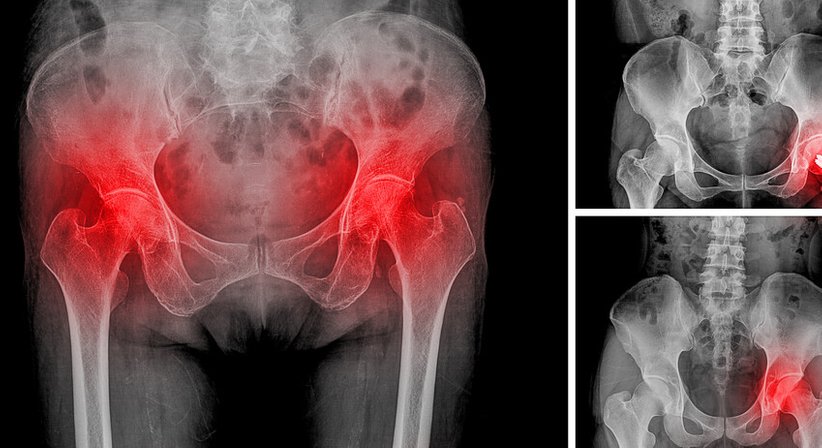

Als Ursache für Hüft- und Leistenschmerzen kommen neben einem geschädigten Hüftgelenk oder Hüftinstabilitäten auch chronische Muskelverspannungen, Bindegewebsverklebungen oder beispielweise auch Schleimbeutelentzündungen in Frage. Akut auftretende Hüftschmerzen sollten in jedem Fall ärztlich abgeklärt werden. Auch bei hartnäckigen chronischen Schmerzen sollten Sie sich an einen Orthopäden wenden.

Im Zentrum der Abklärung akuter und chronischer Hüft(gelenks)schmerzen steht eine entsprechende Funktionsprüfung und eine sorgfältig durchgeführte Anamnese. Durch den Einsatz von hochauflösenden bildgebenden Verfahren kann die Ursache oft schon durch eine umfassende Untersuchung in der Praxis ermittelt werden.